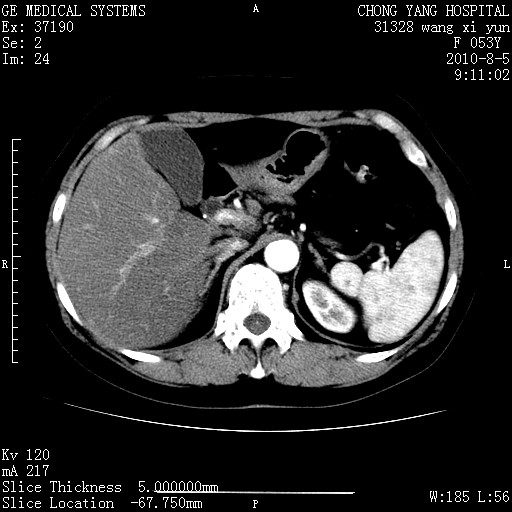

标题: CT28214:F41Y 血尿二十天,建议盆腔平扫加增强。

胆管细胞ca?

1)考虑肝左叶胆管细胞癌。2)脂肪肝。

支持胆管细胞ca。